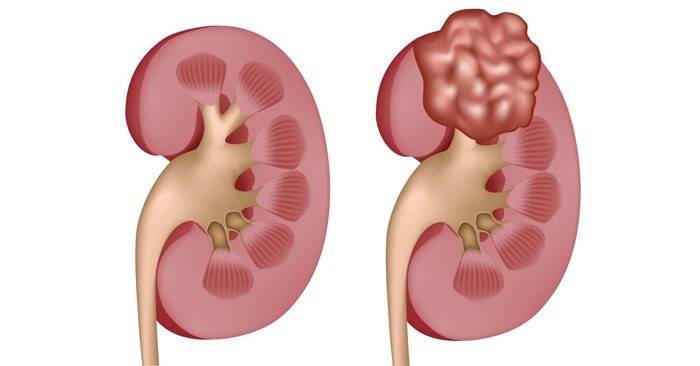

- Поликистоз. В этом случае поражению подлежат одновременно обе почки. Из-за множественного образования кист внешний вид изменяется настолько, что они начинают напоминать виноградные гроздья. Преимущественно генетическая предрасположенность является основным фактором, провоцирующим развитие поликистоза почек.